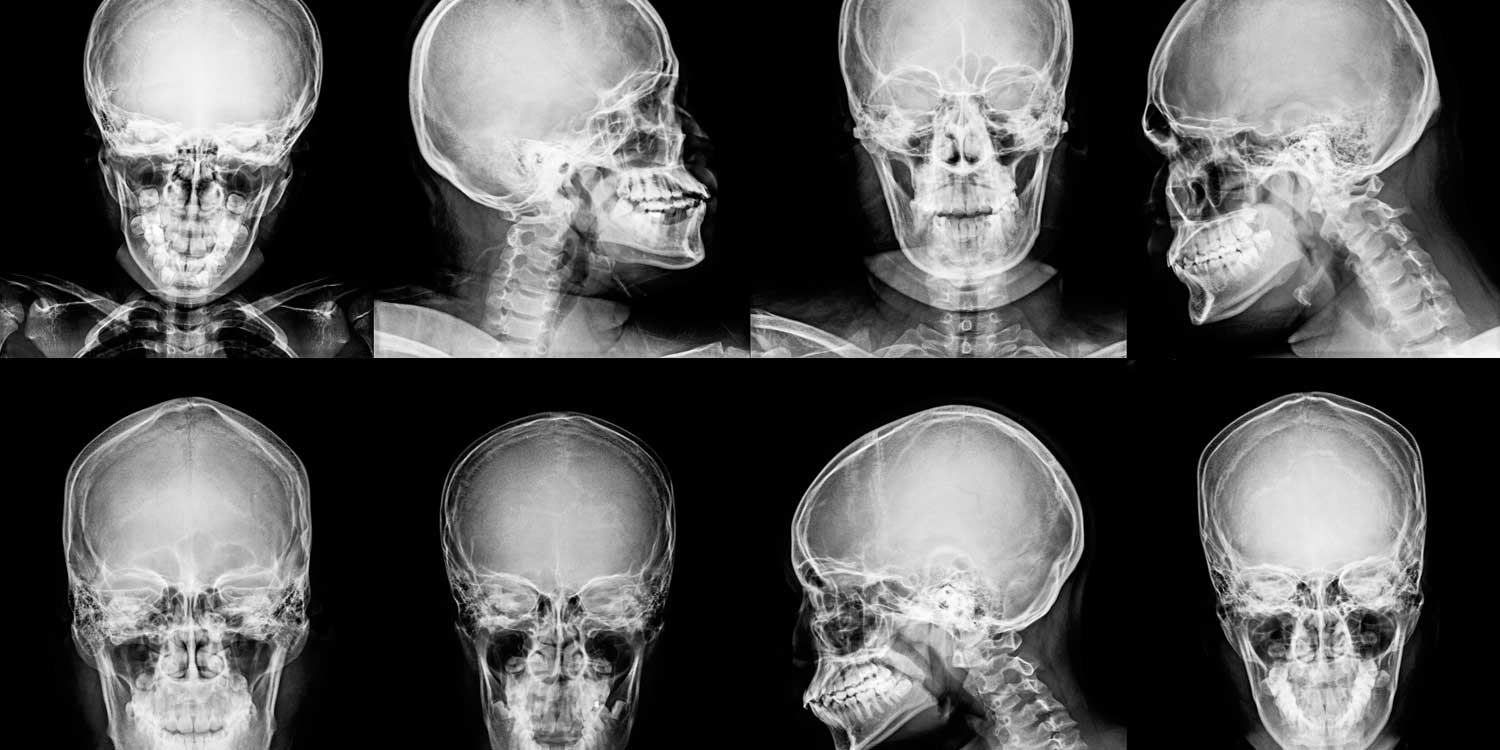

A skull X-ray produces detailed images of the bones of the cranial vault and facial skeleton, allowing your doctor to evaluate fractures, bone lesions, calcifications, and structural abnormalities of the skull. While CT and MRI have largely replaced skull X-rays for head trauma and intracranial evaluation, the skull X-ray retains an important role in specific clinical situations — including the assessment of metabolic bone disease, the initial evaluation of low-risk head injuries, part of skeletal surveys for conditions like multiple myeloma, and medicolegal documentation.

A standard skull series typically includes two to four views. Each is angled to project different parts of the skull without overlapping structures obscuring the detail.

The lateral view is the single most informative projection of the skull and is always included. The patient’s head is turned 90 degrees so the beam passes through one side to the other. It provides an excellent side-profile view of the entire cranial vault, sutures (coronal, lambdoid, sagittal), the sella turcica (the saddle-shaped bony seat of the pituitary gland), and vascular channels. The lateral view is best for detecting linear fractures of the parietal and temporal bones, visualizing the frontal and sphenoid sinuses, and assessing skull thickness and density for conditions like Paget’s disease or myeloma.

The PA (posteroanterior) or Caldwell view is taken with the face directed toward the detector. It provides a frontal view of the skull and shows the frontal bone, orbits, nasal bones, and the relationship of the cranial midline structures. On this view, pineal gland displacement from midline can be assessed and frontal sinus abnormalities are visible.

The Towne’s view (also called the AP axial view) is taken with the beam angled downward from the front, projecting the occipital bone and the foramen magnum forward and free of overlapping structures. It is particularly useful for visualizing the posterior fossa, the occipital bone, the internal occipital protuberance, and the petrous ridges. It is the best view for fractures involving the occipital bone or the posterior vault.